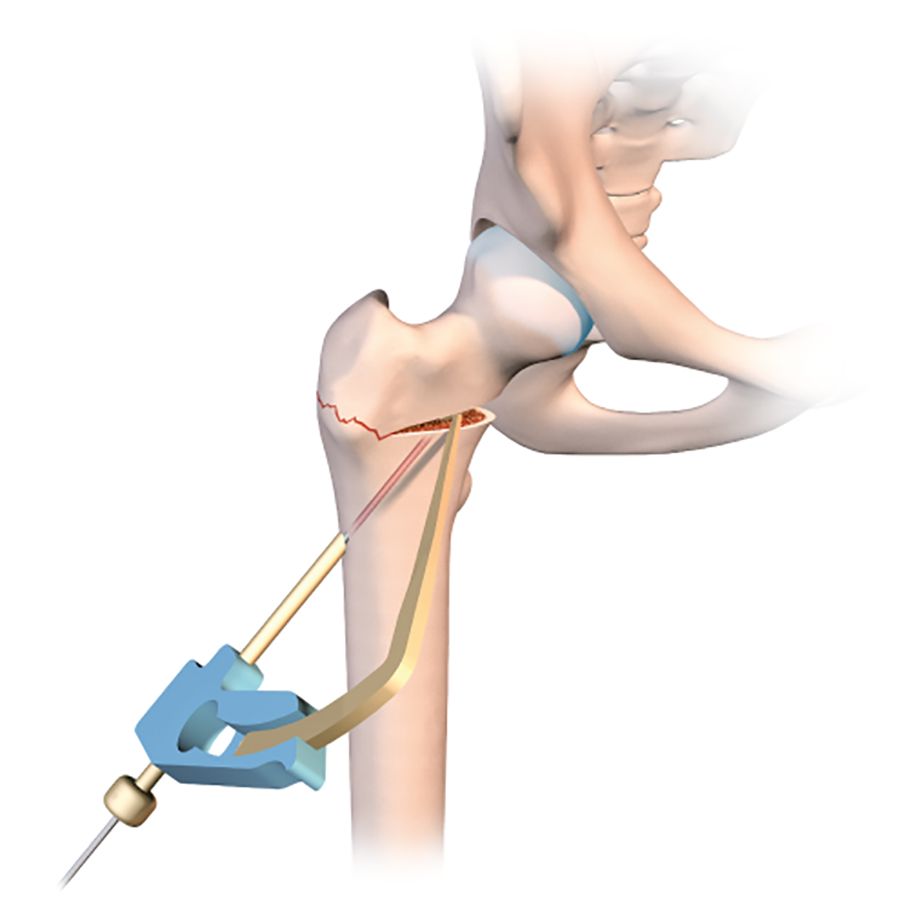

Just before using the orthopaedic table to begin the compression, it is a good idea to use a tibial drill guide (as for cruciate ligament repair) (Figs. 2b, c, d).

This makes it much easier to guide a pin into the osteotomy line that has just been created. The pin should of course sit just within the osteotomy line, without going any further. Applying compression will close the line and fix the pin in the neck and head of femur. With the osteotomy line closed and the pin in place, the final stage is to insert a 7mm cannulated screw to stabilize the fixation. A second or even third screw may be used if necessary. The image intensifier should be used to check the correct placement of the screws (Fig. 2e).

This technique is also very useful for version correction osteotomies at the base of the neck to treat excessive anteversion of the femoral neck. The problem can be corrected at the point of the problem instead of at the femoral diaphysis as when using an intramedullary nail. The need for rotation requires complete mobilisation of the neck, involving a double osteotomy line in order to avoid mobilising the greater trochanter. The first horizontal line terminates at the lower insertion of the greater trochanter on the trochanteric tubercle (Figs 4b and c), with the second line running perpendicular and vertically terminating in the greater trochanter (Fig. 4d) just behind the origin of the femoral neck, leaving the periosteum intact. The line is usually incomplete.

Before making the two osteotomy lines, the whole procedure can be made easier by drilling a 3.5mm hole in the anterior cortex anterior to where the two perpendicular lines will join, then using an image intensifier to ensure the optimal positioning of the two osteotomy lines (Fig 4b).